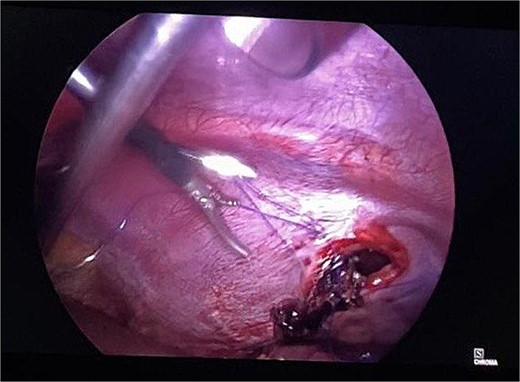

Routine examinations, including total blood counts, differential blood counts, renal function tests, and liver function tests, were within normal limits. The chest X-ray PA view showed the herniation of bowel loops into the left hemithorax with the collapse of the lower zone of the lung with no evidence of previous fracture (Fig. 1). Computed tomography (CT) showed a defect of size around 4 cm with evidence of protrusion of intra-abdominal content in the left hemidiaphragm with basal atelectasis of the left lung and mild dilatation of the jejunal bowel loops with a few air-fluid levels without a transition point (Fig. 2). The patient underwent laparoscopic left diaphragmatic hernia repair with mesh hernioplasty after 6 h of admission. The intraoperative findings revealed a defect of size 4 cm × 2 cm at the posterolateral aspect of the left hemidiaphragm with protrusion of the transverse colon, omentum, and part of the spleen with adhesions (Fig. 3). The content of the hernia was reduced, and primary repair of the defect was done (Fig. 4), and the defect was closed with a 10 × 15 cm intraperitoneal onlay composite mesh (Fig. 5). A postoperative X-ray showed no evidence of herniation of the bowel loops above the left hemidiaphragm (Fig. 6). He was discharged on the fourth postoperative day with oral medications. Follow-up in the outpatient department on the 14th postoperative day showed that he was doing well.

Intraoperative picture showing the defect in the left diaphragm with the omentum and bowel loops as content.

Intraoperative picture following reduction of hernia. The defect is being closed with prolene.